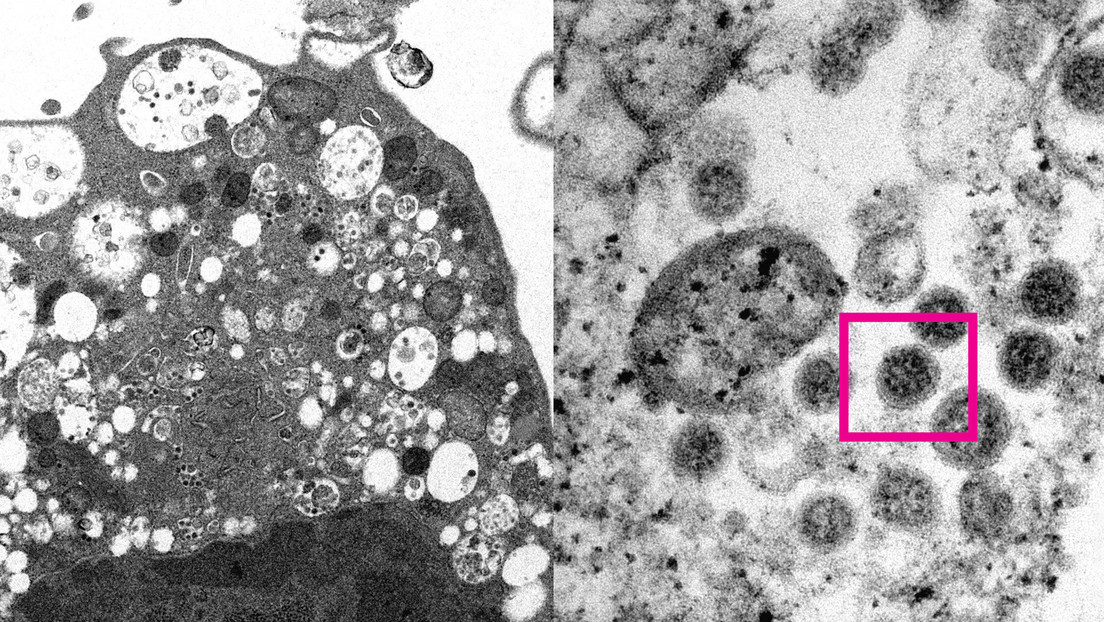

Los investigadores tomaron una micrografía electrónica de una célula de un riñón de un mono infectado con la variante ómicron.

A la izquierda se aprecia el daño celular causado por la infección, en forma de vesículas hinchadas que contienen pequeñas partículas virales negras. A la derecha, un mayor zoom sobre la foto permite distinguir grupos de partículas virales con picos en forma de corona en la superficie (enmarcados en rojo).